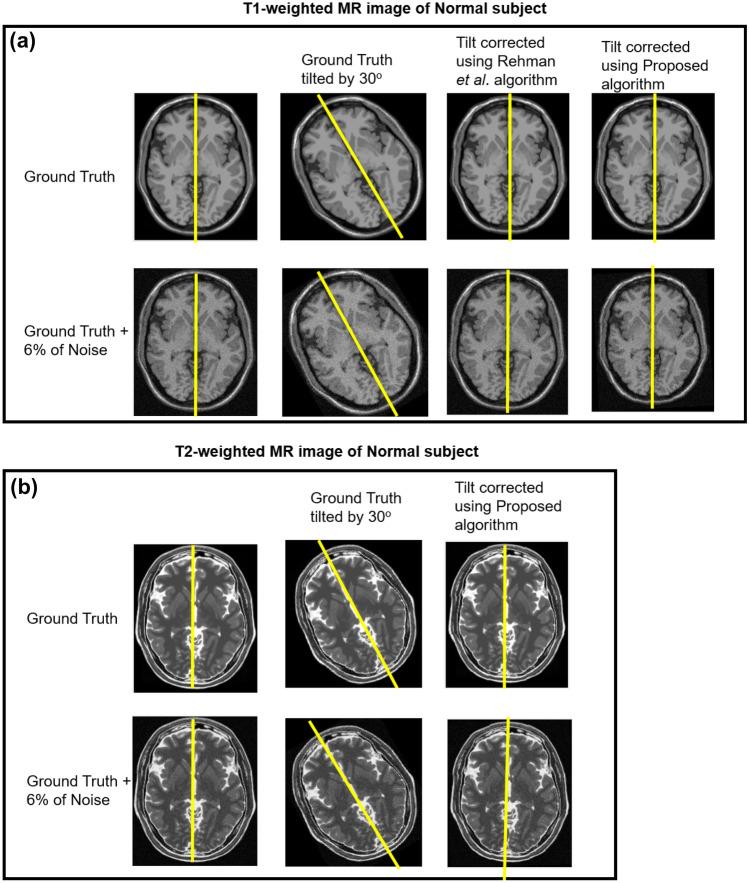

In a general scenario, the brain images acquired from magnetic resonance imaging (MRI) may experience tilt, distorting brain MR images. The tilt experienced by the brain MR images may result in misalignment during image registration for medical applications. Manually correcting (or estimating) the tilt on a large scale is time-consuming, expensive, and needs brain anatomy expertise. Thus, there is a need for an automatic way of performing tilt correction in three orthogonal directions (X, Y, Z). The proposed work aims to correct the tilt automatically by measuring the pitch angle, yaw angle, and roll angle in X-axis, Z-axis, and Y-axis, respectively. For correction of the tilt around the Z-axis (pointing to the superior direction), image processing techniques, principal component analysis, and similarity measures are used. Also, for correction of the tilt around the X-axis (pointing to the right direction), morphological operations, and tilt correction around the Y-axis (pointing to the anterior direction), orthogonal regression is used. The proposed approach was applied to adjust the tilt observed in the T1- and T2-weighted MR images. The simulation study with the proposed algorithm yielded an error of 0.40 ± 0.09°, and it outperformed the other existing studies. The tilt angle (in degrees) obtained is ranged from 6.2 ± 3.94, 2.35 ± 2.61, and 5 ± 4.36 in X-, Z-, and Y-directions, respectively, by using the proposed algorithm. The proposed work corrects the tilt more accurately and robustly when compared with existing studies.

在一般情况下,从磁共振成像(MRI)获得的脑图像可能会倾斜,扭曲脑 MRI 图像。脑 MRI 图像的倾斜可能会导致在医学应用的图像配准过程中出现对位不准。手动(或估计)大范围的倾斜非常耗时、昂贵,并且需要脑部解剖学专业知识。因此,需要一种自动的方法来在三个正交方向(X、Y、Z)上进行倾斜校正。本工作旨在通过分别测量 X 轴、Z 轴和 Y 轴上的俯仰角、偏航角和滚动角来自动校正倾斜。对于围绕 Z 轴(指向上方)的倾斜校正(指向上方),使用图像处理技术、主成分分析和相似性度量。此外,对于围绕 X 轴(指向右侧)的倾斜校正(指向右侧),使用形态学操作和围绕 Y 轴(指向前方)的倾斜校正(指向前方),使用正交回归。该方法应用于调整 T1 和 T2 加权 MRI 中观察到的倾斜。该算法的模拟研究产生的误差为 0.40±0.09°,优于其他现有研究。通过使用该算法,在 X、Z 和 Y 方向上获得的倾斜角度(以度为单位)分别为 6.2±3.94、2.35±2.61 和 5±4.36。与现有研究相比,该方法能更准确、更稳健地校正倾斜。